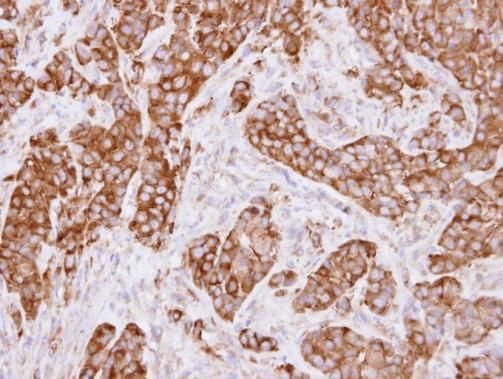

IHC analysis of MVP using anti-MVP antibody. MVP was detected in paraffin-embedded section of human lung cancer tissue. Heat mediated antigen retrieval was performed in citrate buffer (pH6, epitope retrieval solution) for 20 mins. The tissue section was blocked with 10% goat serum. The tissue section was then incubated with 1 µg/ml rabbit anti-MVP Antibody overnight at 4°C. Biotinylated goat anti-rabbit IgG was used as secondary antibody and incubated for 30 minutes at 37°C. The tissue section was developed using Strepavidin-Biotin-Complex (SABC) with DAB as the chromogen.